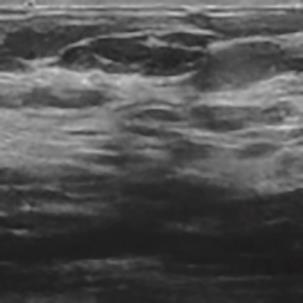

乳腺癌是全球女性最常见的恶性肿瘤之一,准确的病变分割对于乳腺癌的早期诊断与治疗具有重要意义。然而,由于病变形态的多样性以及超声成像机制的复杂性,现有基于深度学习的乳腺超声图像病变分割方法在分割准确性方面仍面临巨大挑战。为进一步提升乳腺超声图像中病变区域的分割精度,该文基于经典U-Net架构,提出了一种新型乳腺超声图像病变分割网络(CWSASKM-BBAM-Net)。首先,在网络中引入逐通道空间自适应选择核卷积模块(CWSASKM),根据不同通道的语义特征为每个空间位置自适应选择感受野大小,以增强多尺度信息的建模能力;然后,引入双向边界感知机制(BBAM),通过融合正向与反向注意力,对目标显著区域及其边界进行协同建模,同时逐步提升对非显著区域与病变区域的区分能力,以进一步强化边界信息的表达;最后,在3组公开乳腺超声图像数据集(BUSI、UDIAT和STU)上开展分割实验。结果表明:该方法在数据集BUSI上的杰卡德指数、精确率、召回率和Dice相似系数分别为71.97%、82.85%、81.40%和80.44%,较次优方法分别提升1.69、1.05、1.28和1.84个百分点;在数据集UDIAT上,这4项指标分别达到78.14%、88.31%、86.73%和86.10%,较次优方法分别提升了2.75、2.04、0.56和2.01个百分点;在外部数据集STU上,该方法也取得了优于其他方法的整体表现。实验结果表明,CWSASKM-BBAM-Net在乳腺超声图像分割任务中展现出更优的整体性能。